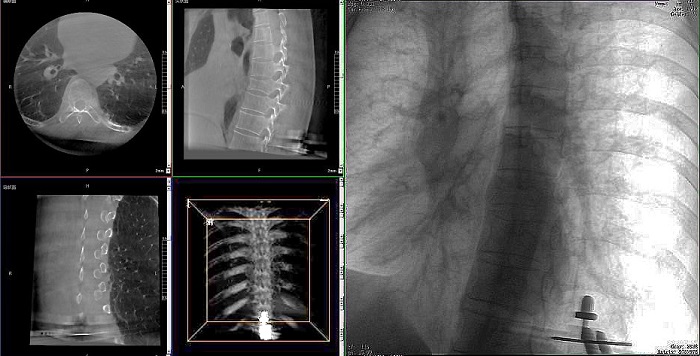

①機器人輔助胸椎手術操作難點之圖像采集

胸椎緊鄰肺部,患者的呼吸運動會造成椎節的相對移動,獲取清晰、穩定的影像較為困難。高質量的影像是精準導航的重要前提,胸椎手術中,如果呼吸造成的移動無法得到有效控制,則會降低導航的精度,增加手術風險。人體深吸氣胸圍與深呼氣胸圍的差值約為6~8厘米。

高清三維成像:普愛醫療精研三維成像技術13年,自研的三維C形臂可為手術提供清晰、穩定的三維圖像,為醫生精準開展胸椎手術提供影像保障。

快速掃描:麻醉師通過適當的呼吸控制,配合三維C形臂的快速掃描模式,可以在短時間內完成圖像采集,減少因呼吸運動造成的圖像干擾。

機器人做胸椎手術

機器人做胸椎手術影像